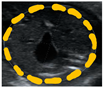

| Abdominal circumference (AC) | Circumference around the edges of a transversal abdominal visualization at stomach/liver level | mm (perimeter), mm2 (area) | ![]() |